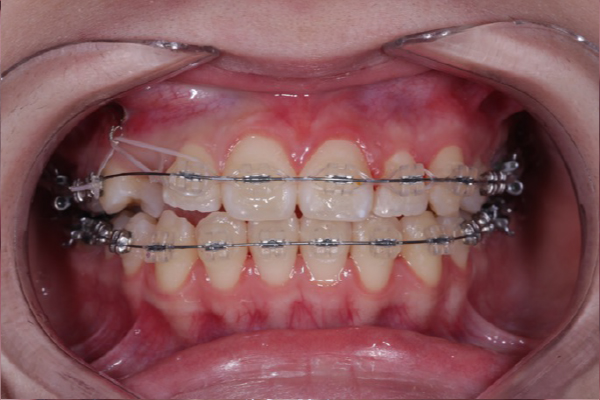

埋まっている犬歯の牽引

残存していた乳犬歯を抜歯後、埋伏している上顎犬歯に対して外科的開窓を行い、矯正装置を用いた牽引を開始しました。

歯列に大きな叢生が認められなかったため、全体的な歯列バランスを維持しながら、スペース管理を行い慎重に犬歯の誘導を進めました。

定期的に歯の移動方向や歯周組織の状態を確認しながら治療を行いました。

本症例では適切なタイミングで診断と介入を行えたことで、矯正的牽引により永久犬歯を歯列内へ誘導することができました。